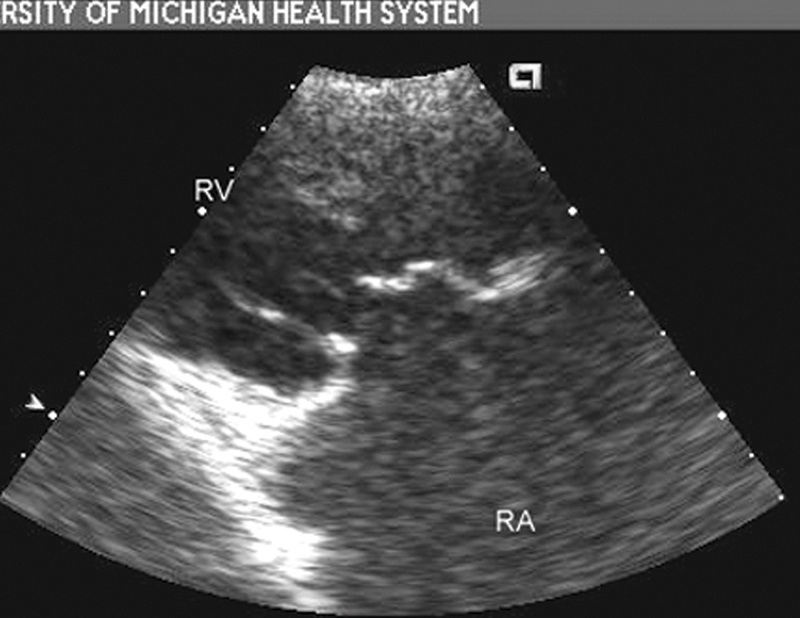

فحوصات تشخيصية لبعض امراض القلب والشرايين التاجية